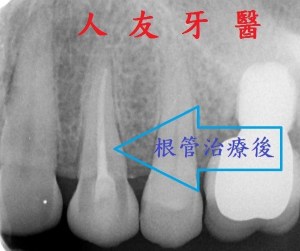

而左側門牙根尖有一個病變,醫師透過根管治療的方式把牙根深層的細菌清除乾淨,放入柱心補強,最後再搭配牙套保護.